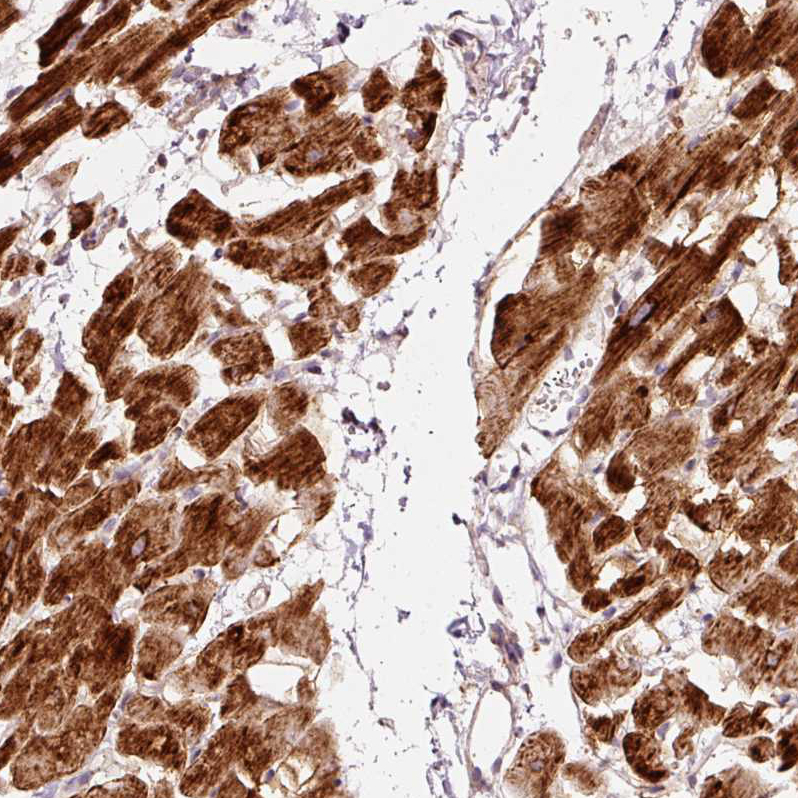

Immunohistochemical staining of human heart muscle shows strong cytoplasmic positivity in cardiomyocytes.